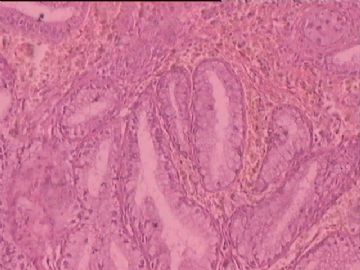

糜烂

图1